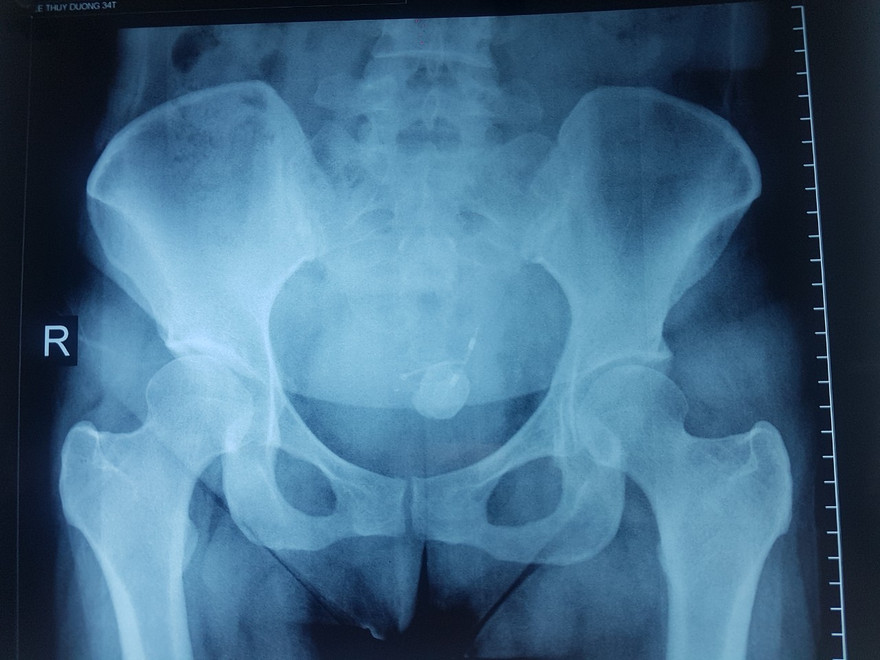

Gắp thành công vòng tránh thai ‘đi lạc’ trong bàng quang nữ bệnh nhân ảnh 1Kết quả chụp phim X-Quang của bệnh nhân.

Ngày 29/4, bệnh nhân đến nhập viện tại  Bệnh viện Hoàn Mỹ Vạn Phúc 2 trong tình trạng tiểu khó (tiểu buốt, tiểu rắt), đau bụng vùng hạ vị. Qua thăm khám kết hợp siêu âm, chụp phim X-quang bác sĩ chẩn đoán sỏi cản quang vùng bàng quang bao quanh một nhánh chữ T của vòng tránh thai (nhánh chữ T đâm xuyên thành bàng quang), một phần của vòng chữ T nằm trong ổ bụng. Người bệnh được chỉ định mổ nội soi tán sỏi bàng quang và lấy vòng tránh thai qua ngả bàng quang. Kết quả ca phẫu thuật thành công lấy hết sỏi bàng quang và lấy vòng trọn vẹn qua ngả bàng quang. Sau khi được lấy vòng ra, sức khỏe của chị D. ổn định, phục hồi tốt và hiện đã được xuất viện trở lại với công việc.